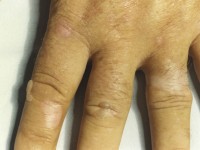

Zie ook tabel 2. VP, HCP, PCT: na zonexpositie bovenmatige kwetsbaarheid van de huid, blaarvorming en littekenvorming met name handen, welke meestal dagen aanhoudt. Tevens kan er hyperpigmentatie en hypertrichose ontstaan in het gelaat. Seizoensgebonden variatie van klachten, waarbij meeste klachten in de zomer en herfst. Risicofactoren voor manifest worden van PCT: hepatitis C, HIV infectie, overmatig alcoholgebruik, haemodialyse bij chronische nierinsufficiëntie,blootstelling aan oestrogenen bij vrouwen. Erythropoietische porfyrie: brandend gevoel, oedeem en erytheem, welke onmiddellijk optreden na zon expositie en weer verdwijnen na een aantal dagen zonvermijding. Tevens kunnen pitting scars in het gezicht gezien worden en periorale rimpelachtige littekens en verdikking van de huid ter plaatse van de knokkels. Klachten seizoensgebonden, met name vroege lente tot late zomer.

Erythropoietische protoporfyrie Erythropoietische protoporfyrie Erythropoietische protoporfyrie